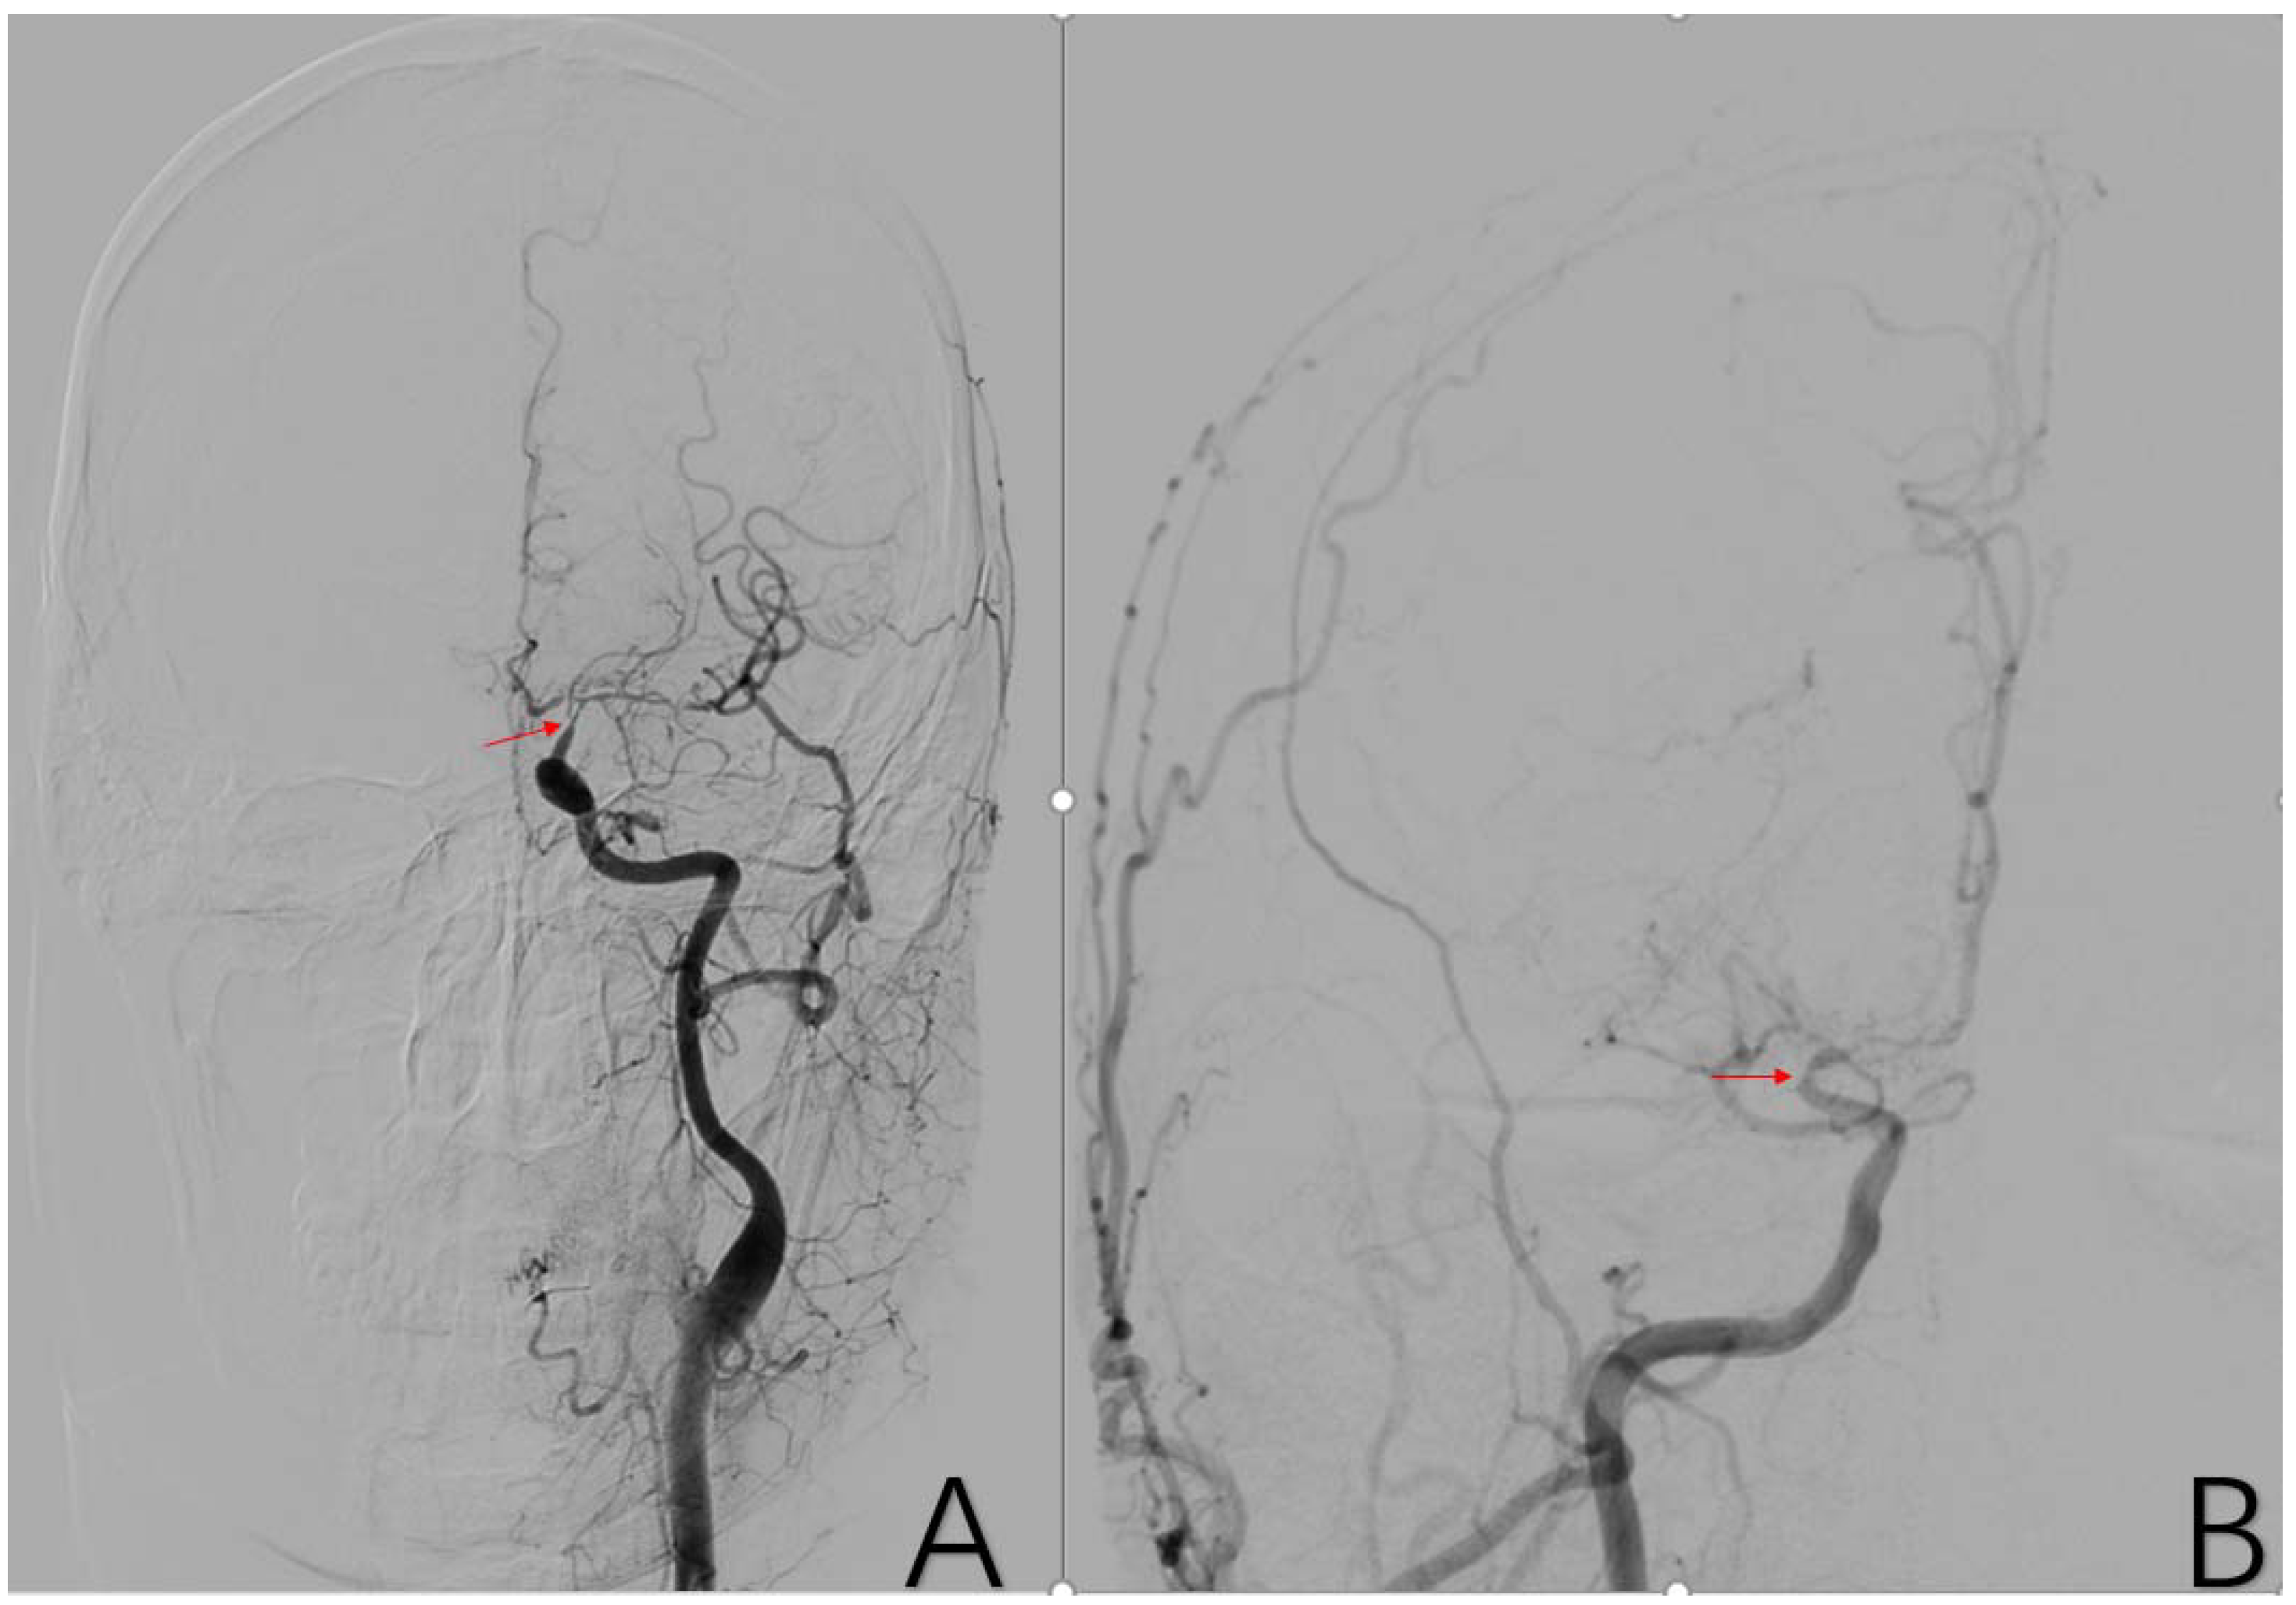

2.3.7. Factor 2 A1 Stenosis

2.3.8. Factor 3 M1 Stenosis

2.3.9. Factor 4 PCA Anomaly

2.3.11. Factor 6 Unstable Compensation